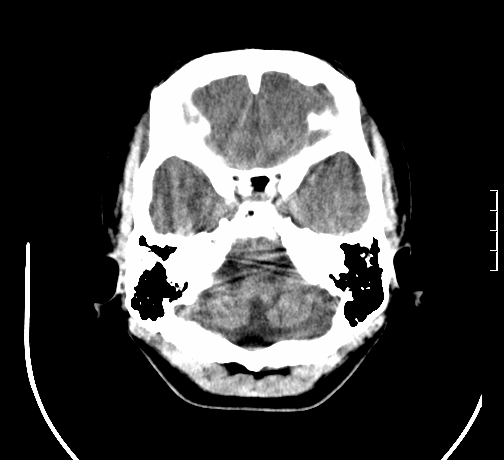

女,28岁,幼时有癫痫,常有发作,服药后可几月不发作,走路不稳3-4月,加重一月。

小脑发育畸形?

小脑萎缩。

考虑小脑发育不良,建议mri检查。

患者出现走路不稳是近几个月的事,而癫痫则有幼时就有,常发,则会常服药,癫痫药可引起小脑综合症,小脑萎缩,而小脑发育不良的主要症状不是癫痫

考虑癫痫,长期间断发服抗癫药,导致小脑综合症,小脑萎缩

不知现在还有没有癫痫,应该另有致痫灶,进一步检查。

考虑小脑发育不良伴小脑萎缩,建议mri检查。

小脑萎缩,原因待查,建议mri检查。

考虑小脑发育不良伴小脑萎缩,建议mri检查

考虑药物性小脑萎缩